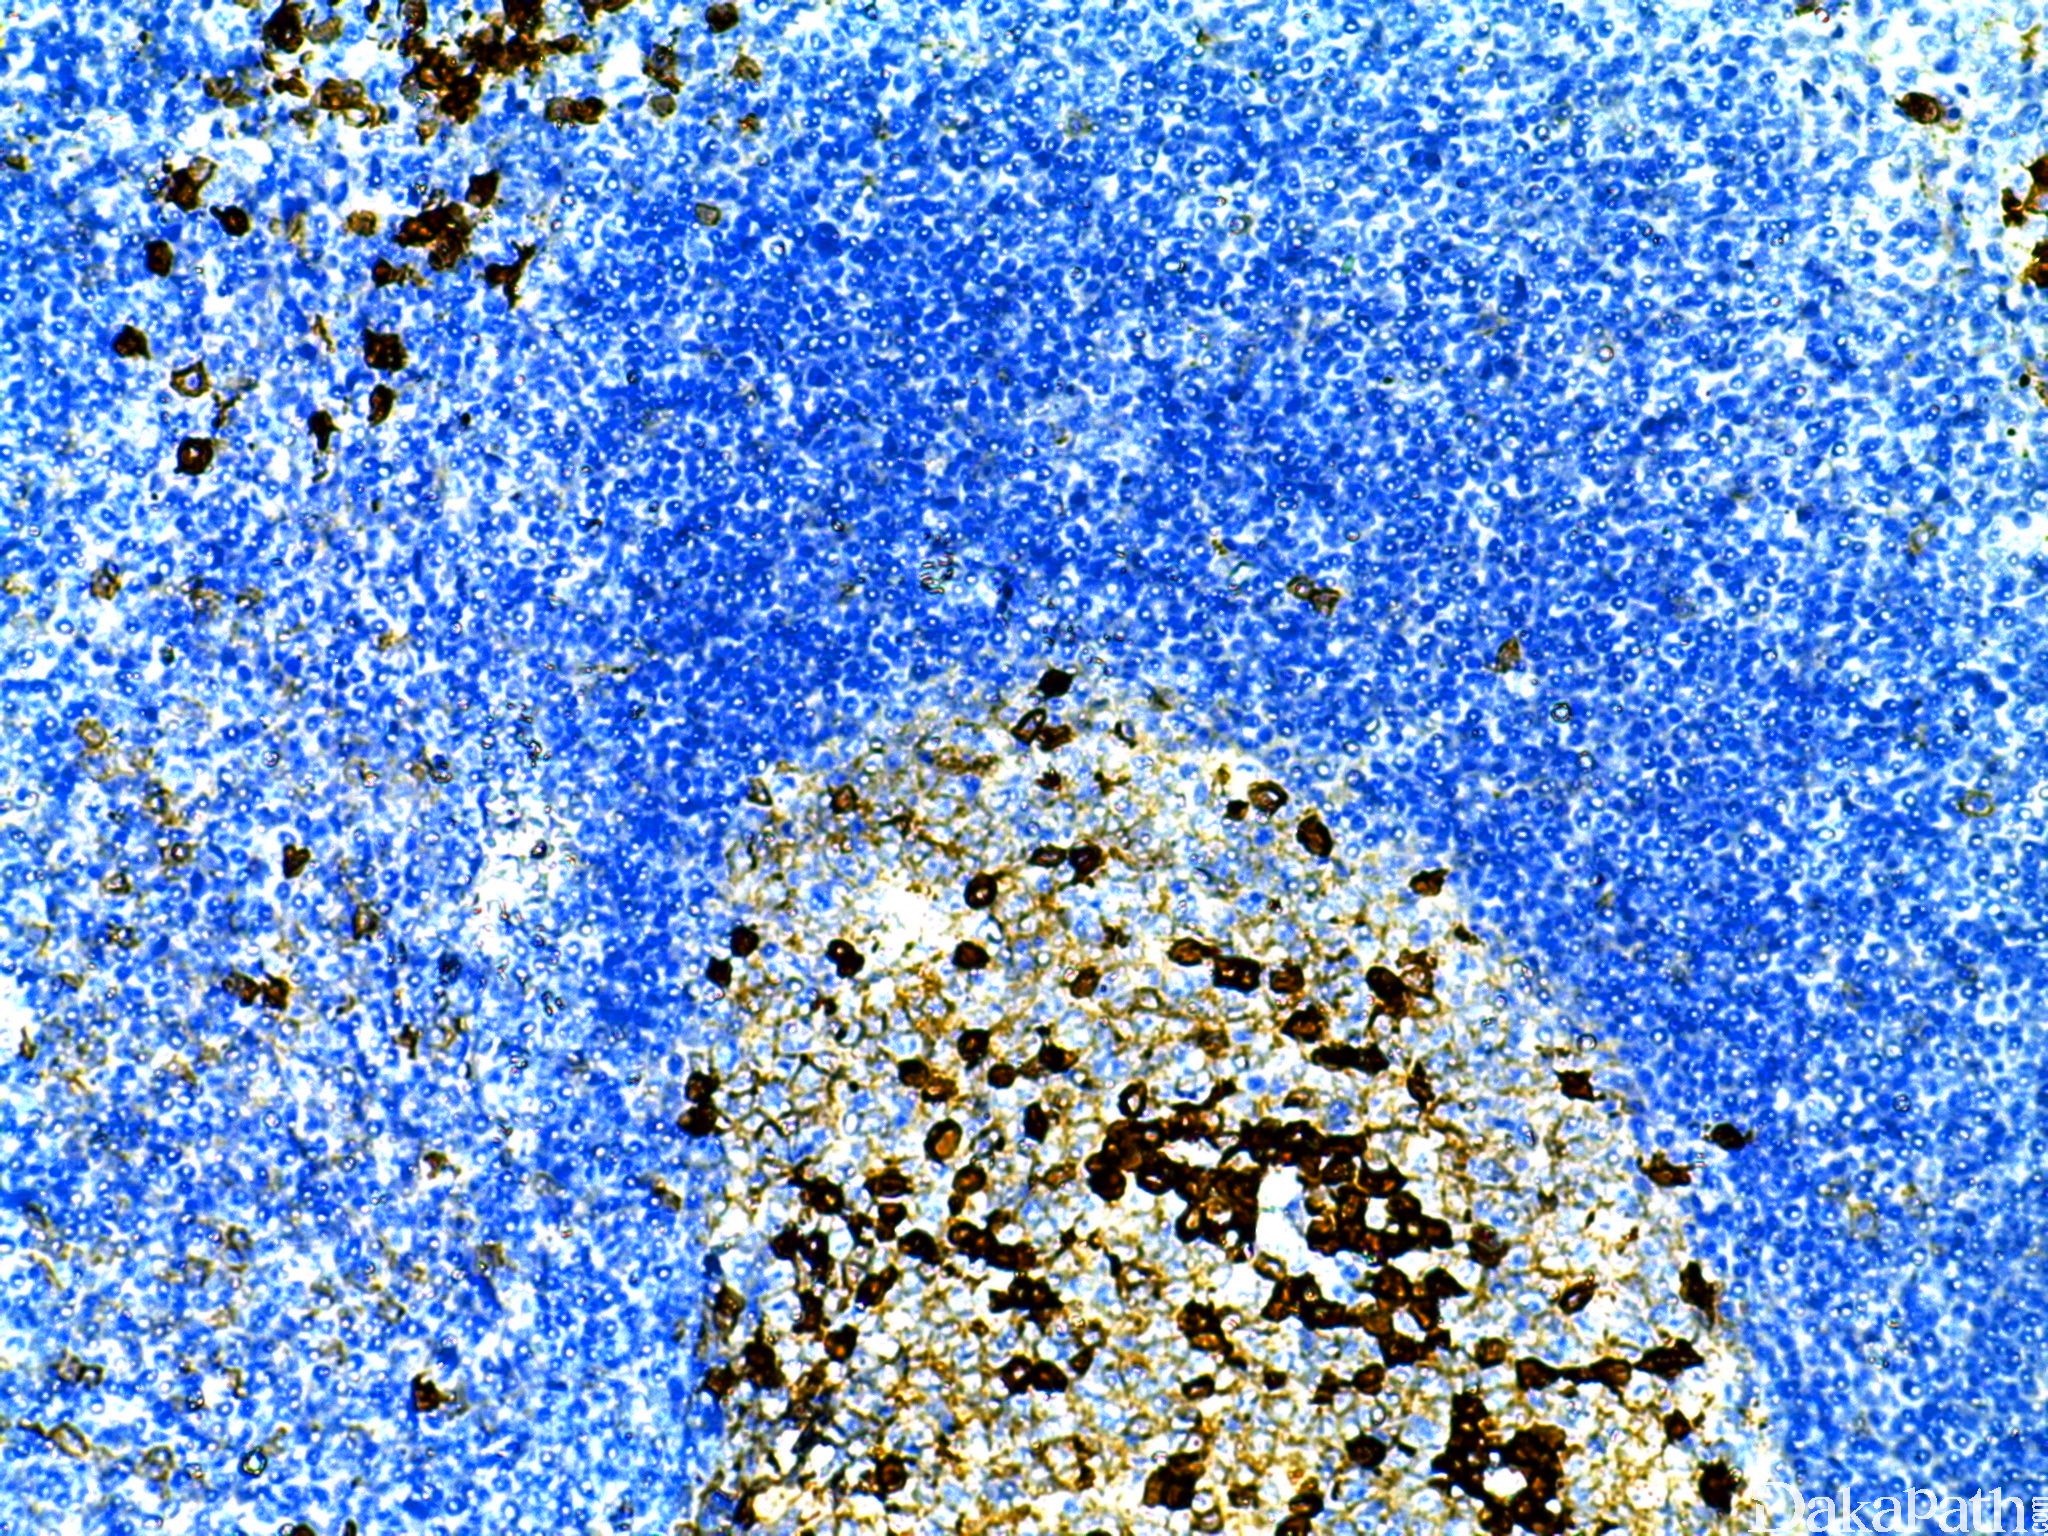

CD38

分子量 46KD 的穿膜糖蛋白,浆细胞强表达,活化的 T、 B 细胞及 NK 细胞亦有表达。

浆细胞肿瘤的诊断。

- Identify plasma cells and plasmablastic differentiation

- Diagnosis of myeloma